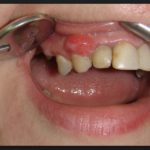

Каждому человеку важно знать, как на любом этапе выглядит рак десны и как проявляется – это поможет вовремя насторожиться и проконсультироваться с врачом. Опухоль замечают не сразу, потому что небольшое уплотнение не ощущается, а эстетически оно малозаметно, и человек не придает ему значения. Когда заболевание прогрессирует, образование быстро разрастается, сопровождаясь определенными признаками. Когда у человека рак десны, начальная стадия, симптомы включают в себя появление на тканях белесых или багровых пятен. Также наблюдается:

- Отеки – в месте поражения возникают припухлости. Иллюстрируют, как выглядит в таком случае рак десны, фото в интернете на сайте клиник, которые занимаются лечением онкологических недугов.

Очень важно знать, как рак десны выглядит и как проявляется на всех стадиях, чтобы вовремя обратить внимание на тревожные симптомы. На начальном этапе опухоль небольшая – ее размер доходит до 1 см в диаметре, а внешне она малозаметна. Второй этап – фаза активного роста образования. Возникает рак десны, 2 стадия которого характеризуется углублением очага заболевания примерно на 1 см. Также появляется первый метастаз, хотя это может произойти только на третьей стадии, когда метастазы обнаруживают в лимфоузлах со стороны пораженной области.